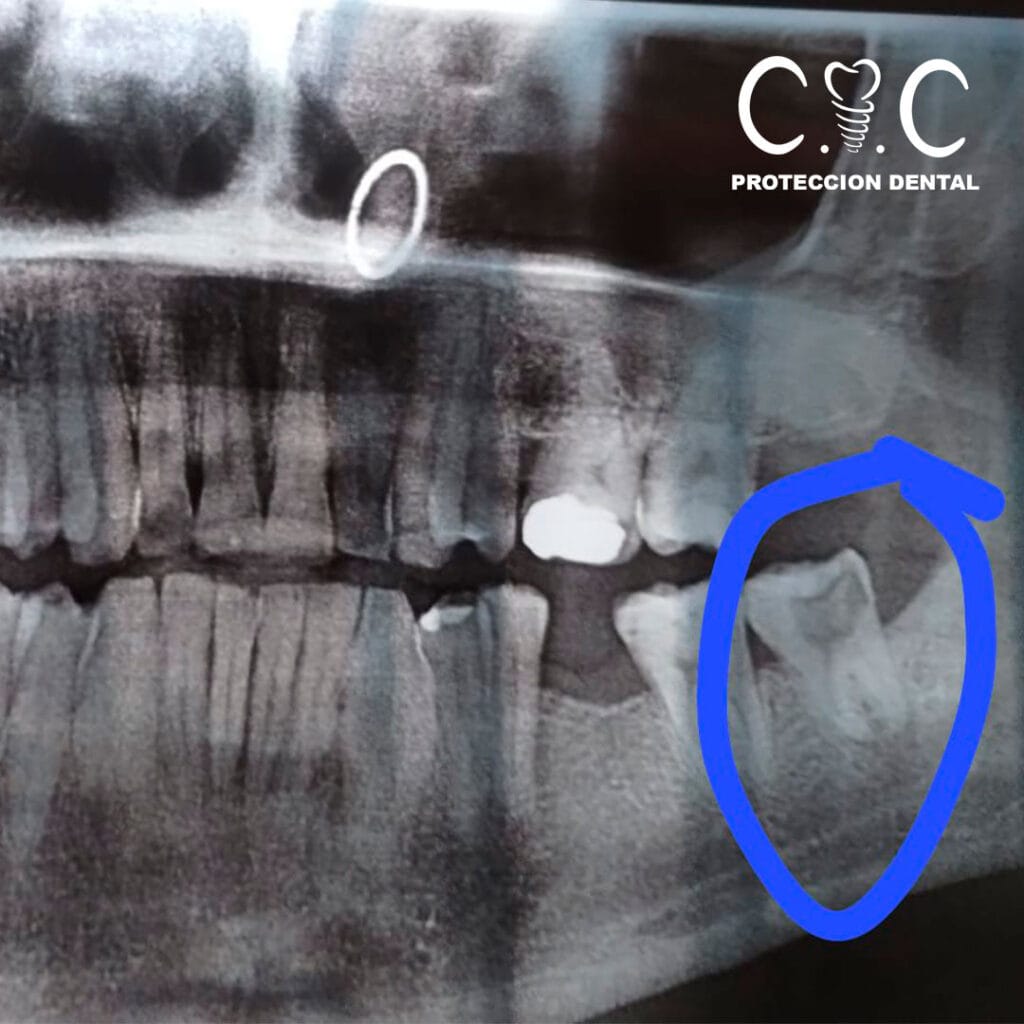

Confía en nuestros especialistas para un tratamiento seguro y sin molestias. Ofrecemos control post extracción, seguimiento personalizado y la tranquilidad de leer los comentarios de pacientes satisfechos. Recuerda que es necesario contar con una radiografía previa y evaluación de la pieza a tratar. Si el dolor te está molestando, ¡no esperes más y consúltanos hoy mismo!

A veces, la extracción de una pieza dental es la mejor solución para proteger tu salud bucal. En Protección Dental, realizamos extracciones dentales con la máxima profesionalidad y cuidado, priorizando tu bienestar.